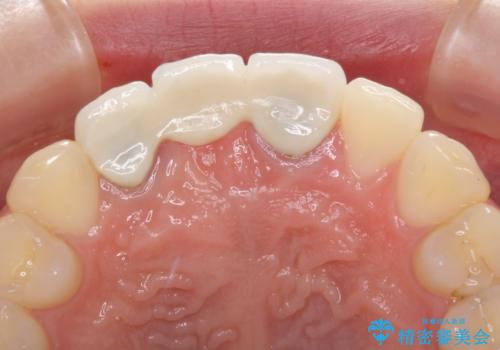

前院では、土台の金属を除去することは不可能であると言われたとのことでした。金属の土台が残っているとセラミックにグレーの金属色が透けて見えてしまうため、拡大鏡やマイクロスコープを用いて丁寧に除去し、天然歯の色に近いファイバーコアを植立することとしました。

また、歯とクラウンの境目が合っていない部分が多く、歯肉からの出血が認められました。